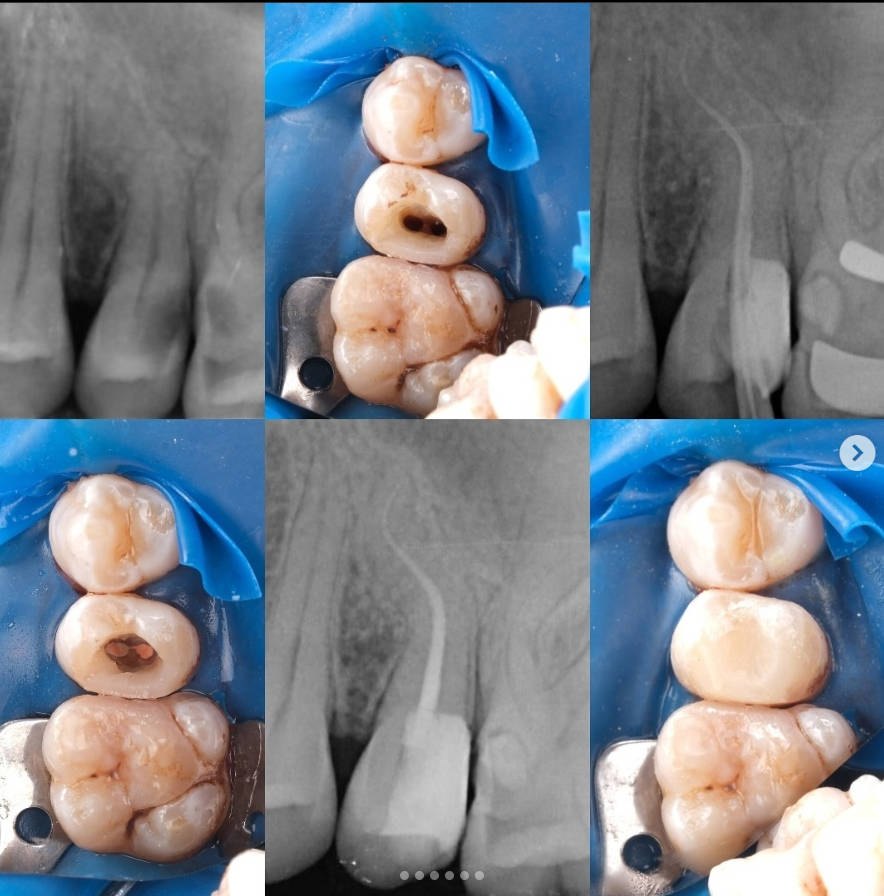

📌 Tooth #25 – Root Canal Treatment Case

📍 Diagnosis:

• The patient presented to the clinic with spontaneous pain, and a diagnosis of irreversible pulpitis was made, indicating the need for root canal treatment.

• The roots exhibit two curvatures, and although there are two canals, they converge at a single apical foramen.

🔧 Treatment Steps:

1. A rubber dam was placed.

2. A pre-endo build-up was performed and the cavity was converted to Class I.

3. The canals were prepared without using any hand files, using only the Perfect Super System Advanced Kit, in the following sequence:

10/.07 → 10/.04 → 17/.05 → 25/.04

Copious irrigation and ultrasonic activation were used throughout preparation.

4. A working length radiograph was taken with gutta-percha cones to confirm canal length.

5. The treatment was completed in a single visit, using a bioceramic root canal sealer.